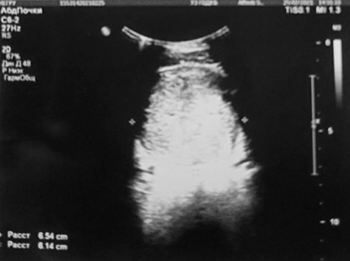

Обследование: ОАК (анемия умеренной степени, СОЭ 21 мм/ч); ОАМ (эритроциты, лейкоциты в большом количестве, белок 0,29, бактерии); БАК: Д-димеры 401 мкг/мл; ликвор (глюкоза 5,8); КТ головного мозга: гиподенсивный участок в левой теменно-затылочной зоне — участок ишемии (?); МРТ ГМ: мультифокальные билатеральные участки гиперинтенсивности в бассейне кровоснабжения сосудов задней циркуляции. (МР-картина может соответствовать синдрому задней обратимой энцефалопатии, васкулиту, эмболическим инфарктам мозга различной степени давности (?)); УЗИ ОБП: гидронефроз с обеих сторон, гиперплазия лимфоузлов; УЗИ мочевого пузыря: весь мочевой пузырь заполнен неоднородными массами, без признаков кровотока, в толще этих масс лоцируется катетер, жидкостной компонент не прослеживается (см. рис. 1); УЗИ БЦА: без патологии; ЭхоКГ: без патологии.

Рисунок 1. Результаты УЗИ мочевого пузыря.